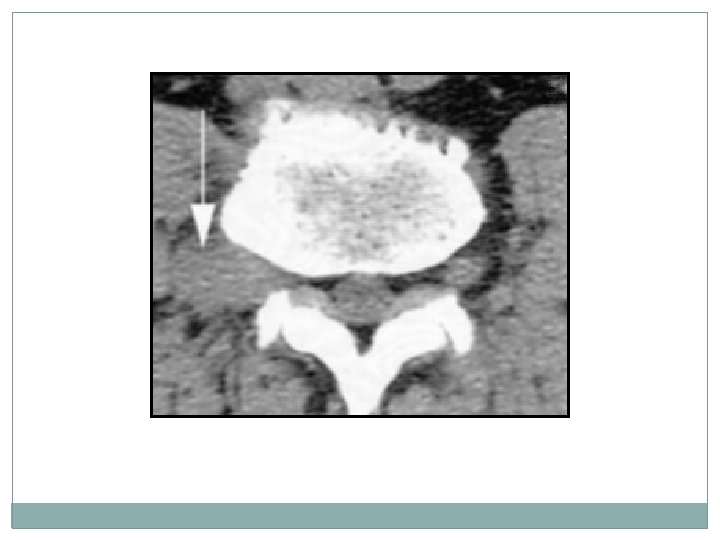

imagerie � 2 La tomodensitométrie (TDM) du rachis lombo sacré: permet de préciser l’HERNIE DISCALE son siège, de son volume, sa migration, son environnement osseux.